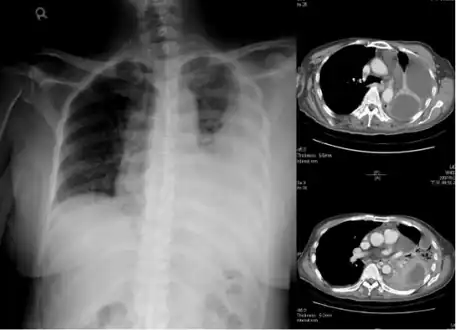

Lungs

Empyema

Empyema with abscess